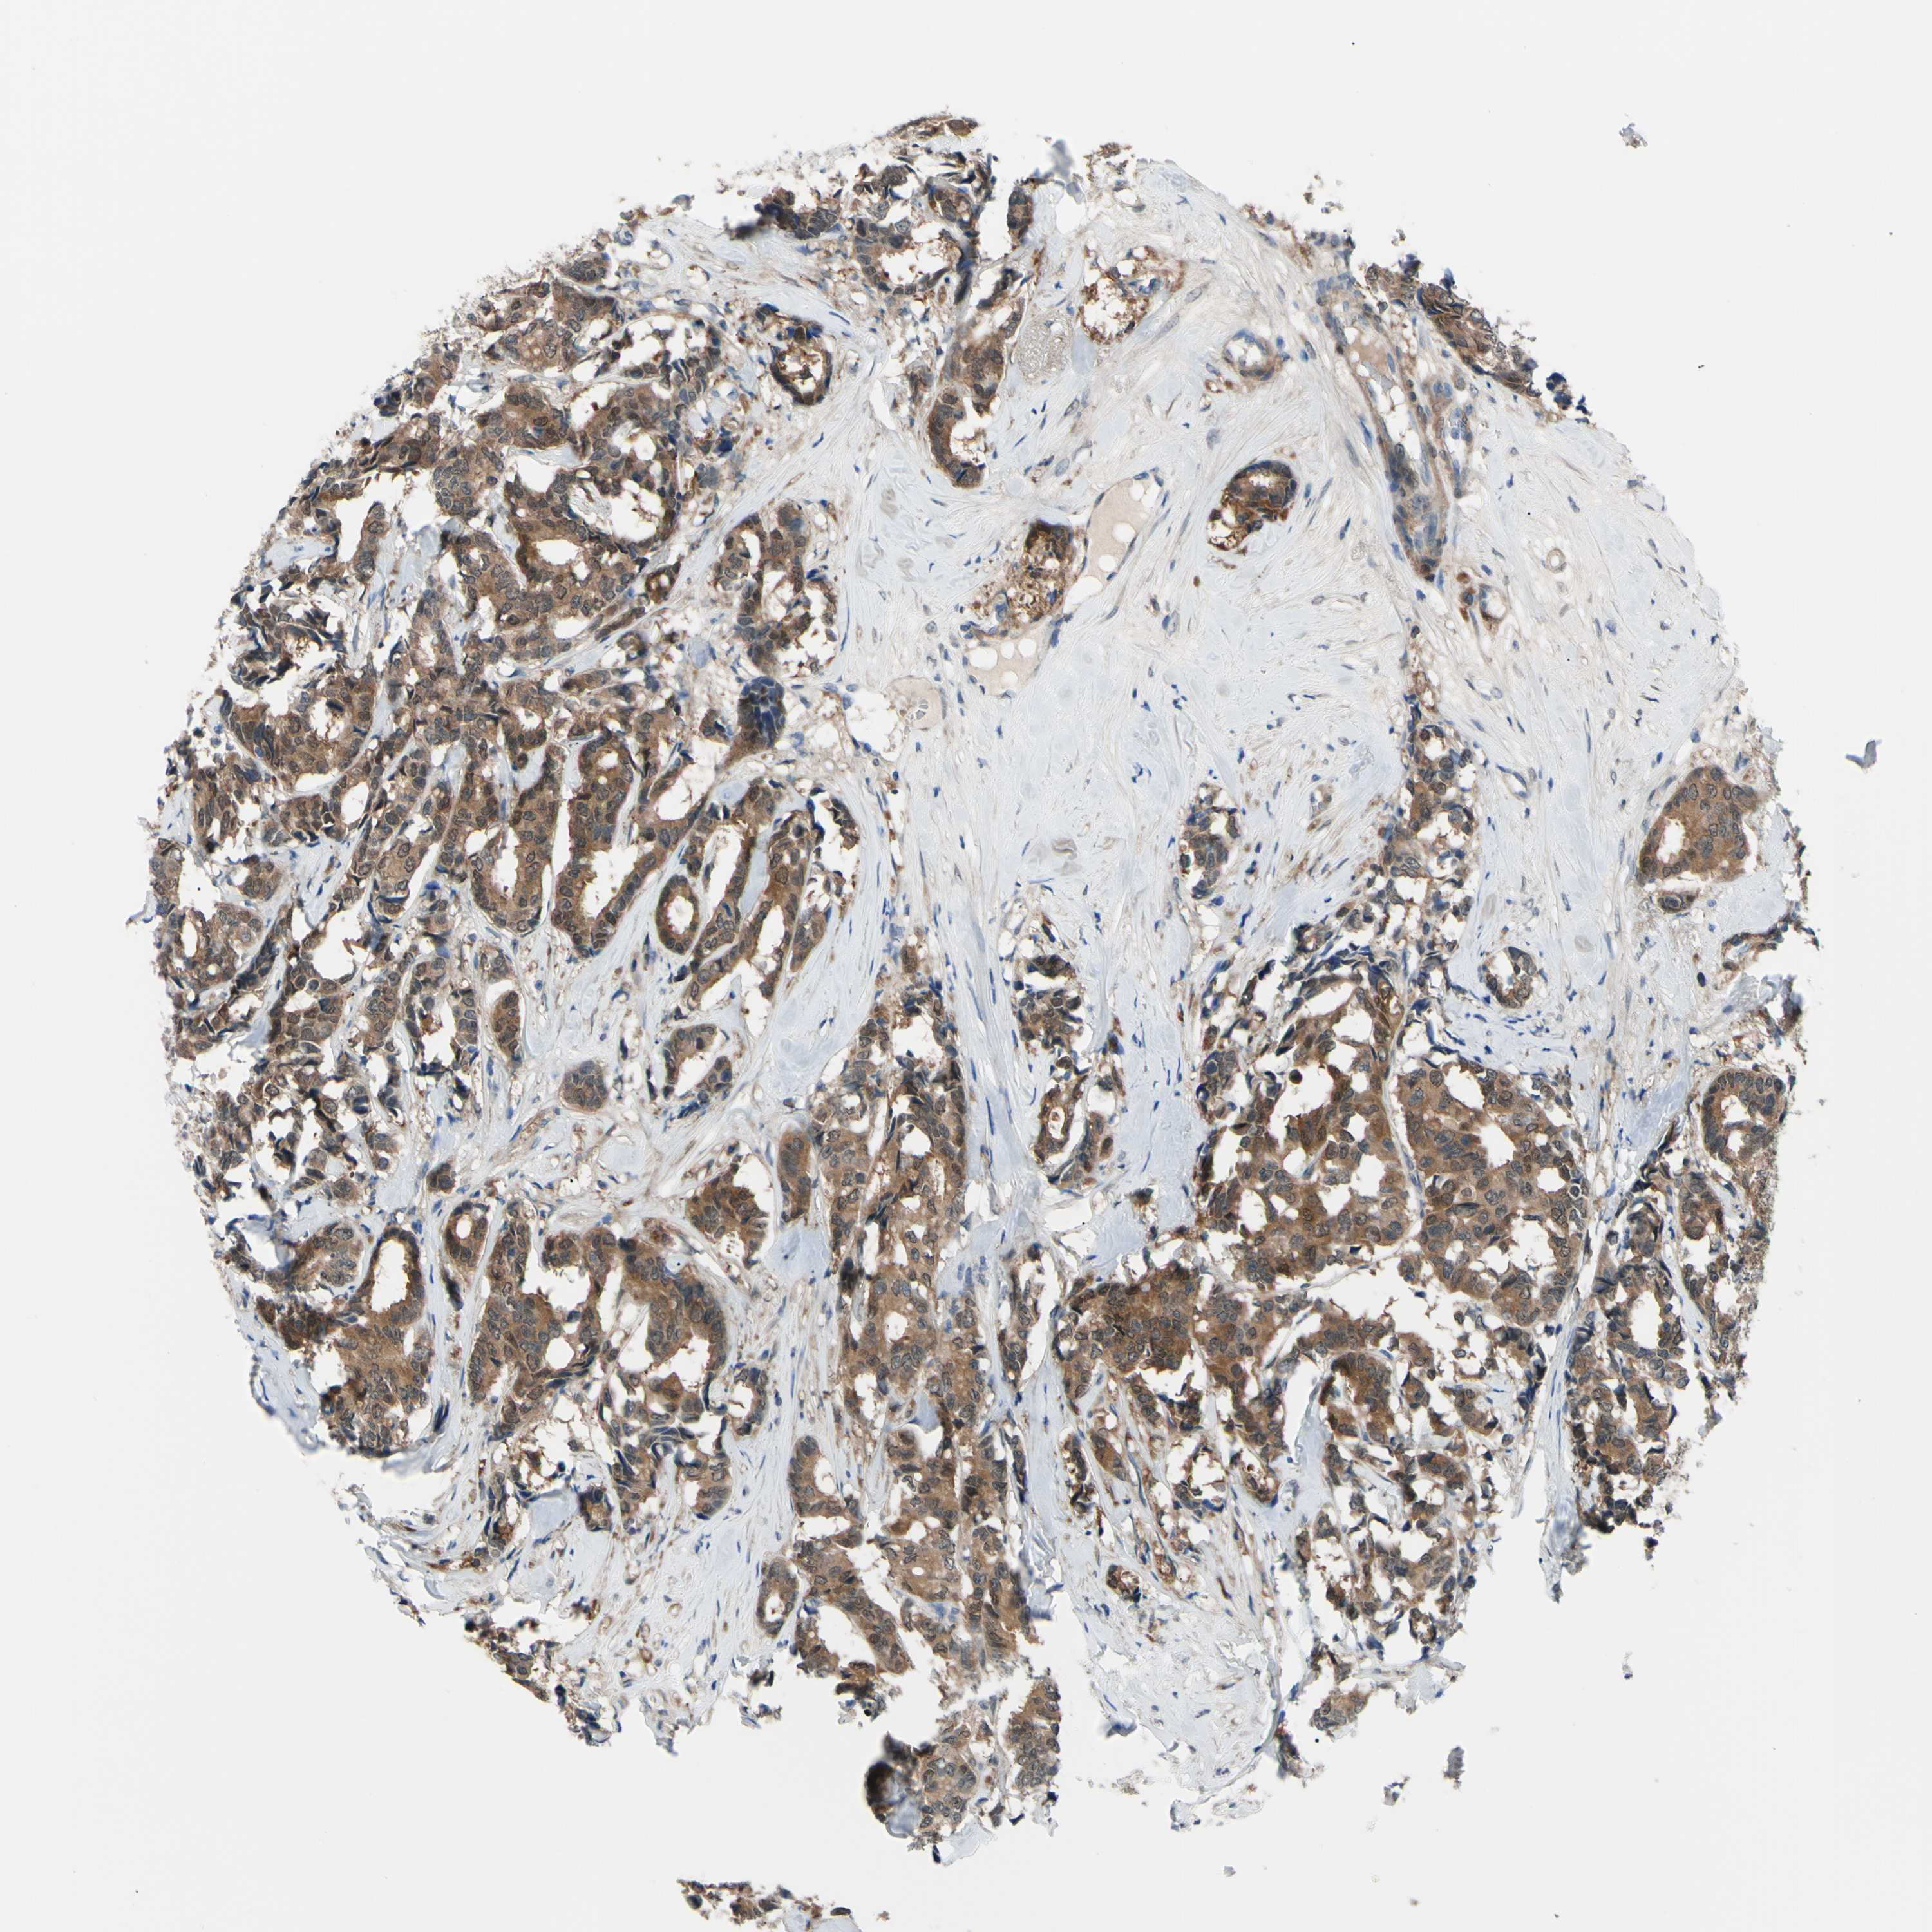

Breast cancer

Human cancer

NOL3 is potential prognostic, high expression is unfavorable in Breast Invasive Carcinoma (TCGA)